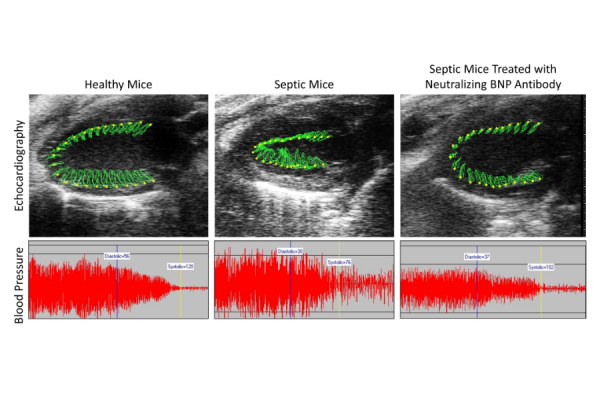

The suppressive effect of sepsis in heart function and blood pressure, which is reversed following treatment with a monoclonal antibody that neutralizes the function of BNP.

In separate experiments, the researchers blocked either JNK activation, using a chemical inhibitor, or BNP activity, using an antibody against the protein that was developed in Dr. Drosatos's laboratory. Both approaches restored blood pressure in septic mice, though JNK inhibition yielded the most robust benefits. Inhibition of either molecule also led to improvements in survival from sepsis.